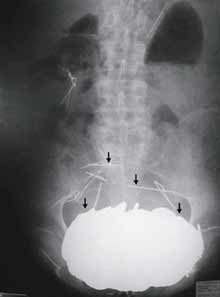

An X-Ray, made of the stomach of a 62-year-old man who came to the emergency room of Cholet General Hospital in western France in 2002. [AP Photo]

Still, doctors were awed when they took an X-ray. They discovered an enormous opaque mass in his stomach that turned out to weigh 12 pounds — as much as some bowling balls. It was so heavy it had forced his stomach down between his hips.

A few details of the Frenchman's case were presented Jan. 1 along with the X-ray — but no explanation of the stomach mass — as a challenge to New England Journal of Medicine readers in a fixture called "A Medical Mystery."

Dr. Lindsey Baden, an editor at the journal, reported that 666 readers in 73 countries — mostly doctors or doctors-in-training — contacted the journal to try to solve the mystery. Almost 90 percent settled on diagnoses consistent with pica, but only 8 percent correctly identified coins.